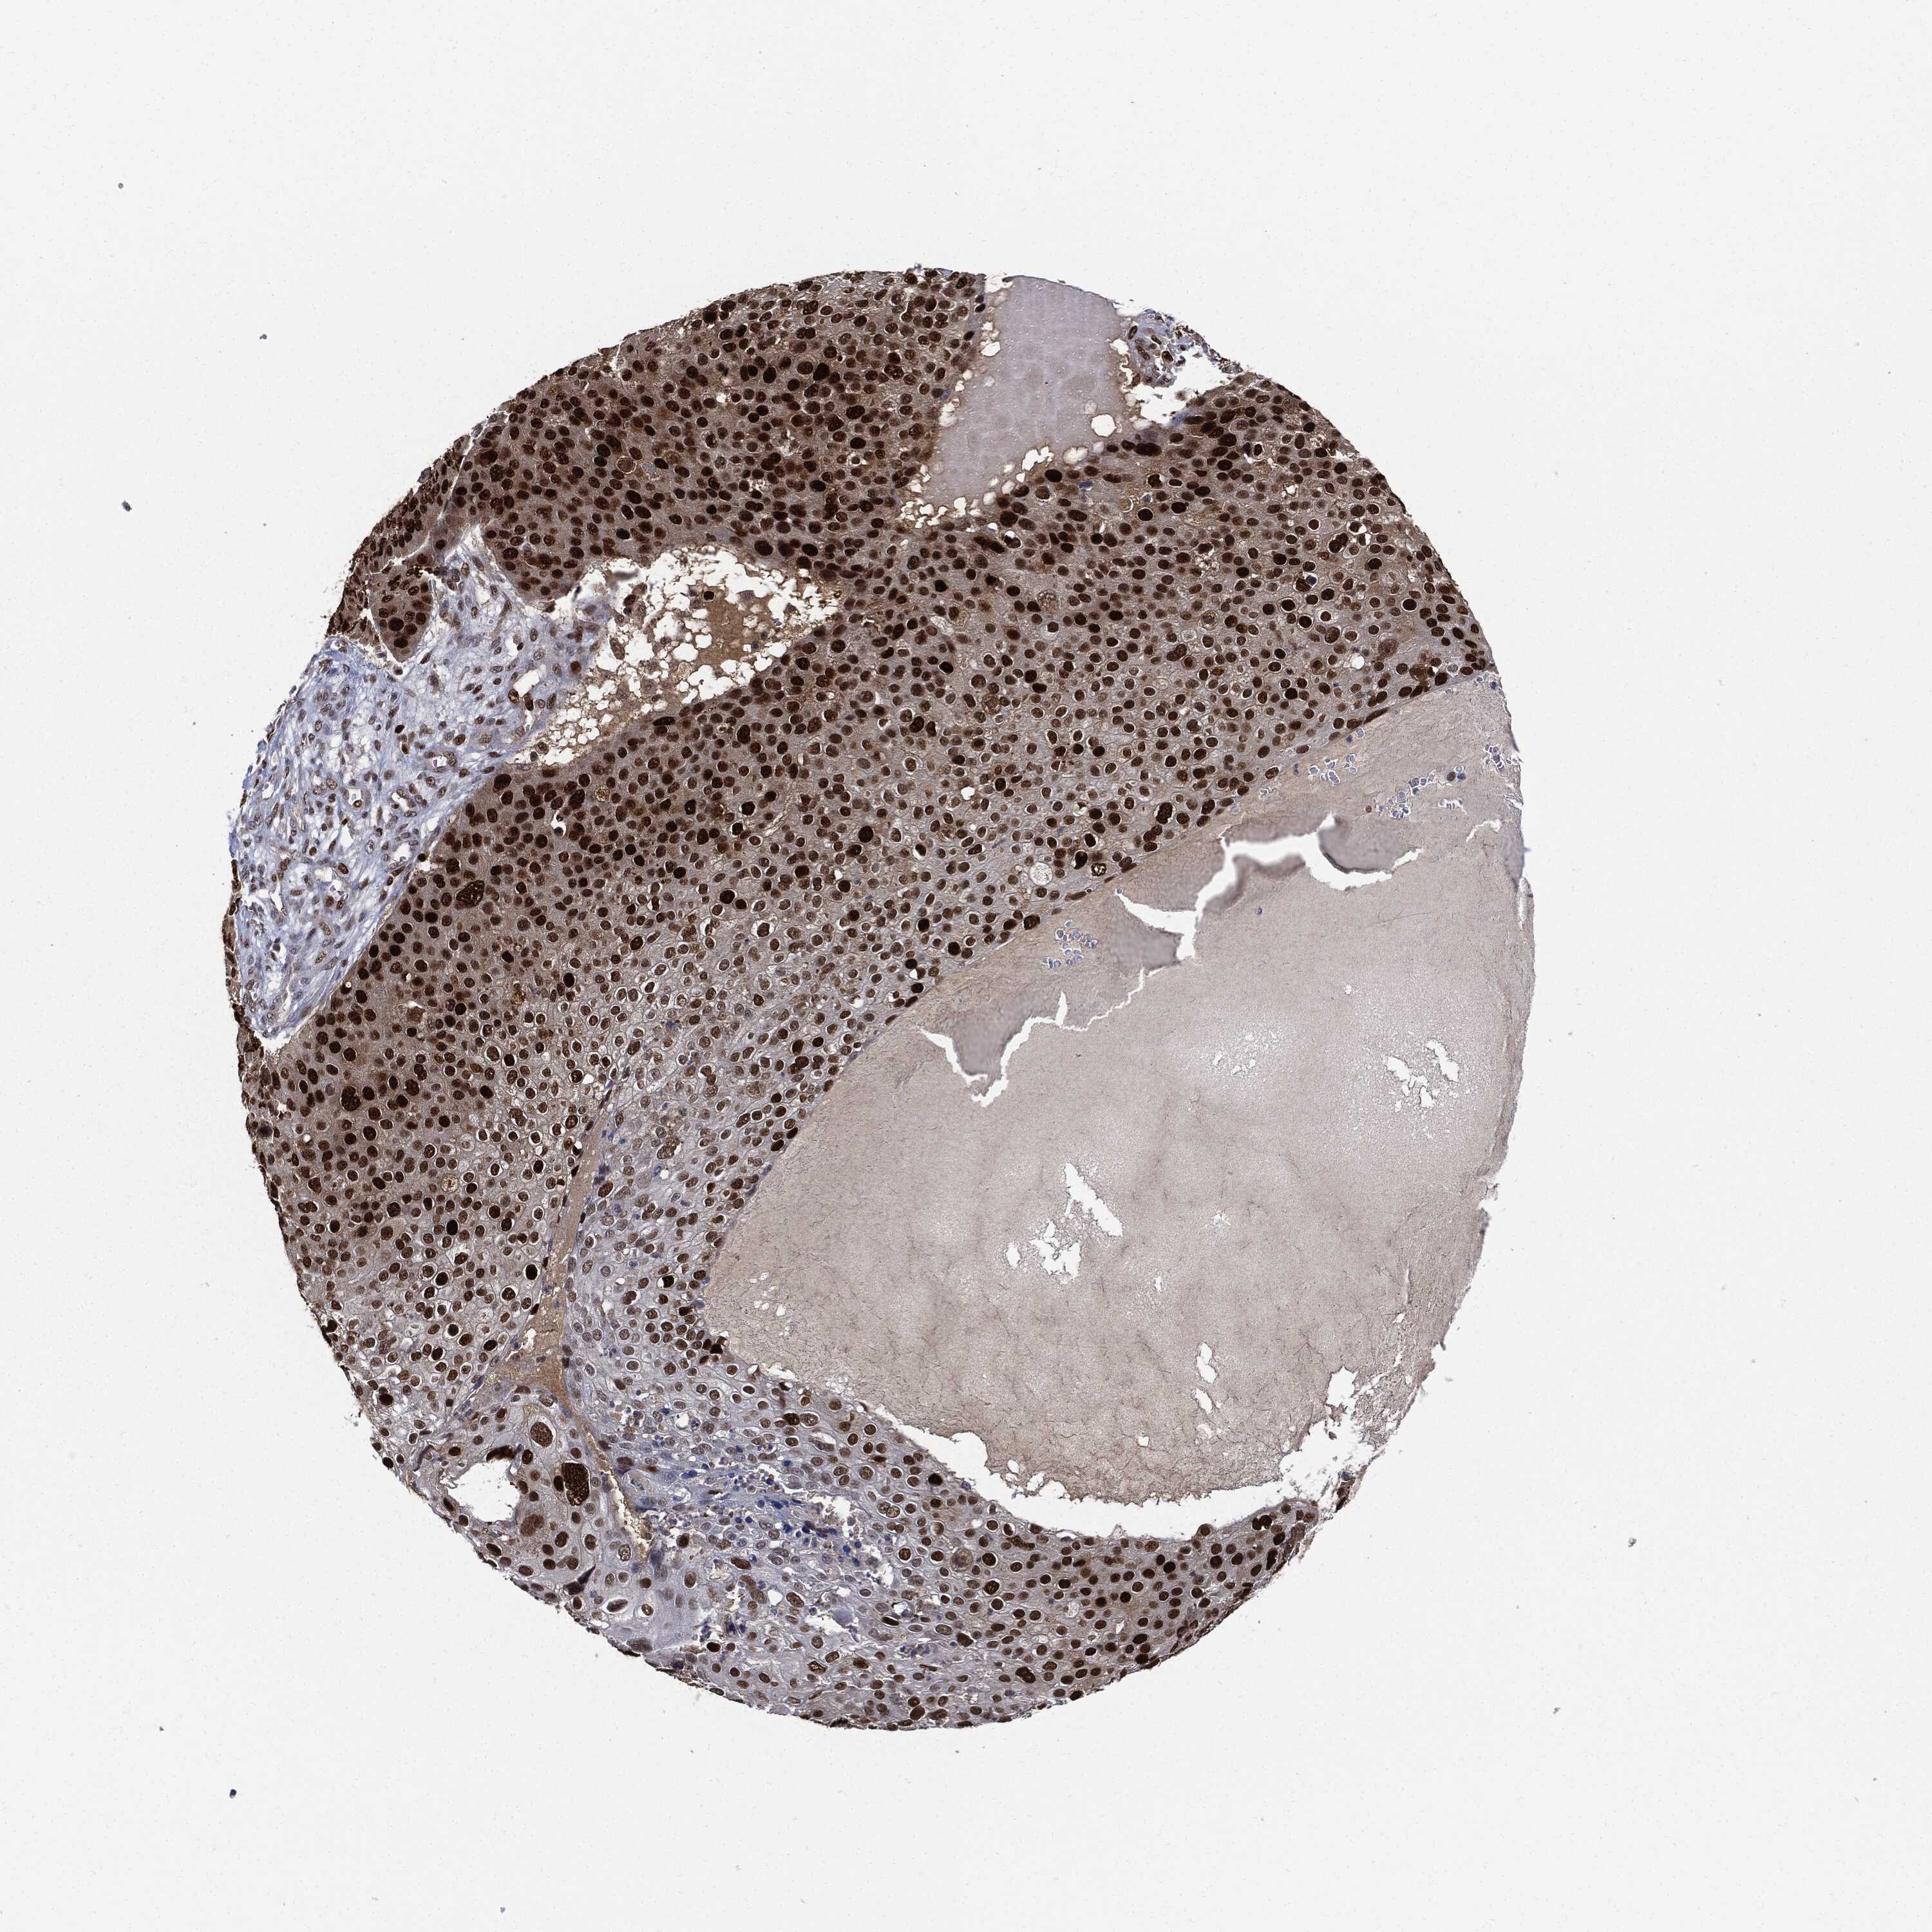

SKIN CANCER - Protein expressioni

A mouse-over function shows sample information and annotation data. Click on an image to view it in a full screen mode. Samples can be filtered based on level of antibody staining by selecting one or several of the following categories: high, medium, low and not detected. The assay and annotation is described here.

Antibody stainingi

Antibody staining in the annotated cell types in the current human tissue is reported as not detected, low, medium, or high, based on conventional immunohistochemistry profiling in selected tissues. This score is based on the combination of the staining intensity and fraction of stained cells.

Each image is clickable and will lead to virtual microscopy that enables deeper exploration of all samples and also displays staining intensity scores, fraction scores and subcellular localization as well as patient and tissue information for each sample.

HPA030521

HPA030522

HPA030523

CAB000148

CAB080240

CAB080241

CAB080242

Staining

High

Medium

Low

Not detected

Intensity

Strong

Moderate

Weak

Negative

Quantity

>75%

75%-25%

<25%

None

Location

Nuclear

Cytoplasmic/membranous

Cytoplasmic/membranous,nuclear

Basal cell carcinoma

Squamous cell carcinoma, NOS

Squamous cell carcinoma, metastatic, NOS